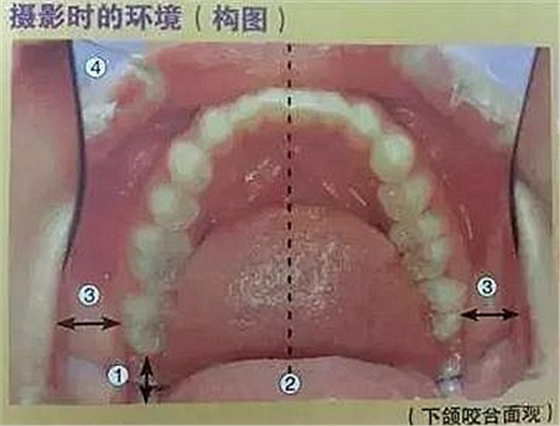

六、咬合面的拍攝

口腔攝影方法與技巧

①反光板離開(kāi)最后磨牙,不要接觸

②正中線位于反光板中央

③反光板邊緣與左右磨牙的間隙一定

④口角拉鉤打開(kāi)的幅度大于反光板寬度

⑤反光板開(kāi)口角度盡可能大(能觀察到前牙區(qū)的舌側(cè))

⑥第一磨牙的咬合平面與焦點(diǎn)吻合

⑦拍攝比例:1:2.4,光圈f22、27,快門速度1/125,閃光強(qiáng)度M/4